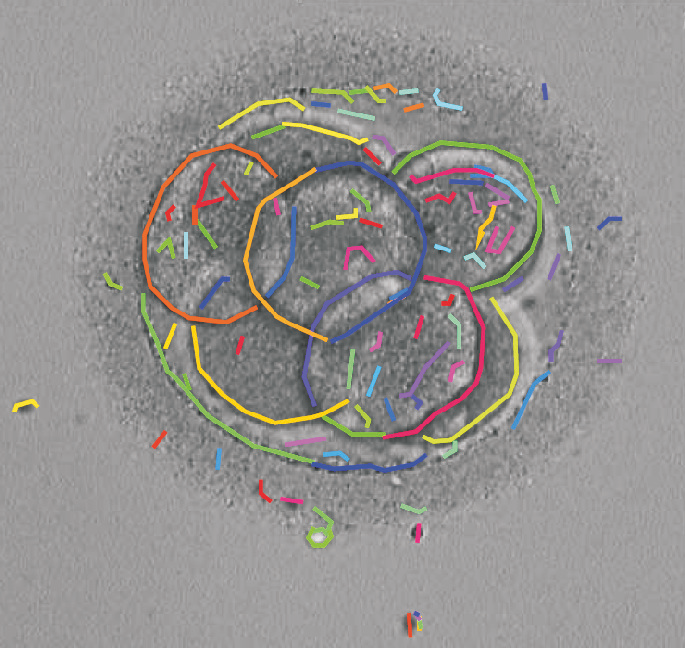

We present a novel method for identification of the boundary of embryonic cells (blastomeres) in Hoffman Modulation Contrast (HMC) microscopic images that are taken between day one to day three. Identification of boundaries of blastomeres is a challenging task, especially in the cases containing four or more cells. This is because these cells are bundled up tightly inside an embryo's membrane and any 2D image projection of such 3D embryo includes cell overlaps, occlusions, and projection ambiguities. Moreover, human embryos include fragmentation, which does not conform to any specific patterns or shape. Here we developed a model-based iterative approach, in which blastomeres are modeled as ellipses that conform to the local image features, such as edges and normals. In an iterative process, each image feature contributes only to one candidate and is removed upon being associated to a model candidate. We have tested the proposed algorithm on an image dataset comprising of 468 human embryos obtained from different sources. An overall Precision, Sensitivity and Overall Quality (OQ) of 92%, 88% and 83% are achieved.